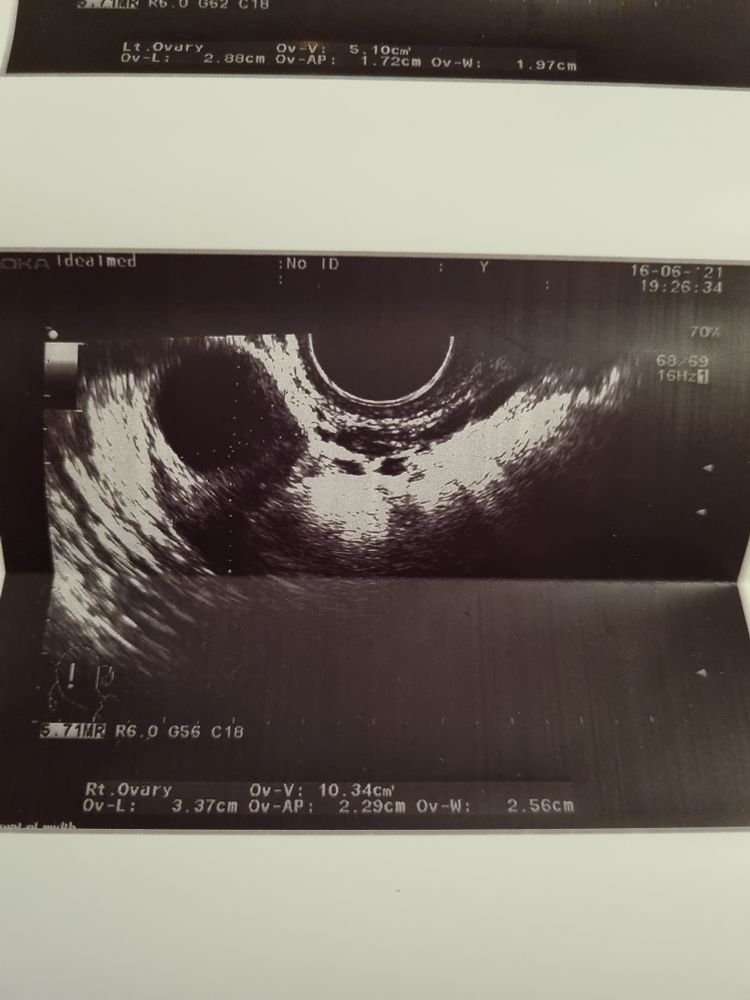

16.06 тянул ПЯ где и был доминантный. Вечером на фоликулометрии врач нашла только фоликул 16. Сказала,что возможно была овуляция, но это не точно,жидкости нет,и не похоже на жёлтое тело.